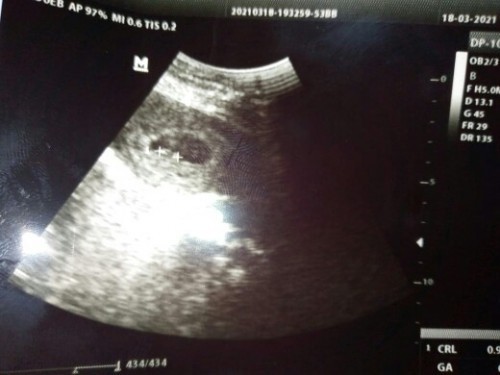

aku 7w3d juga masih kantung bund